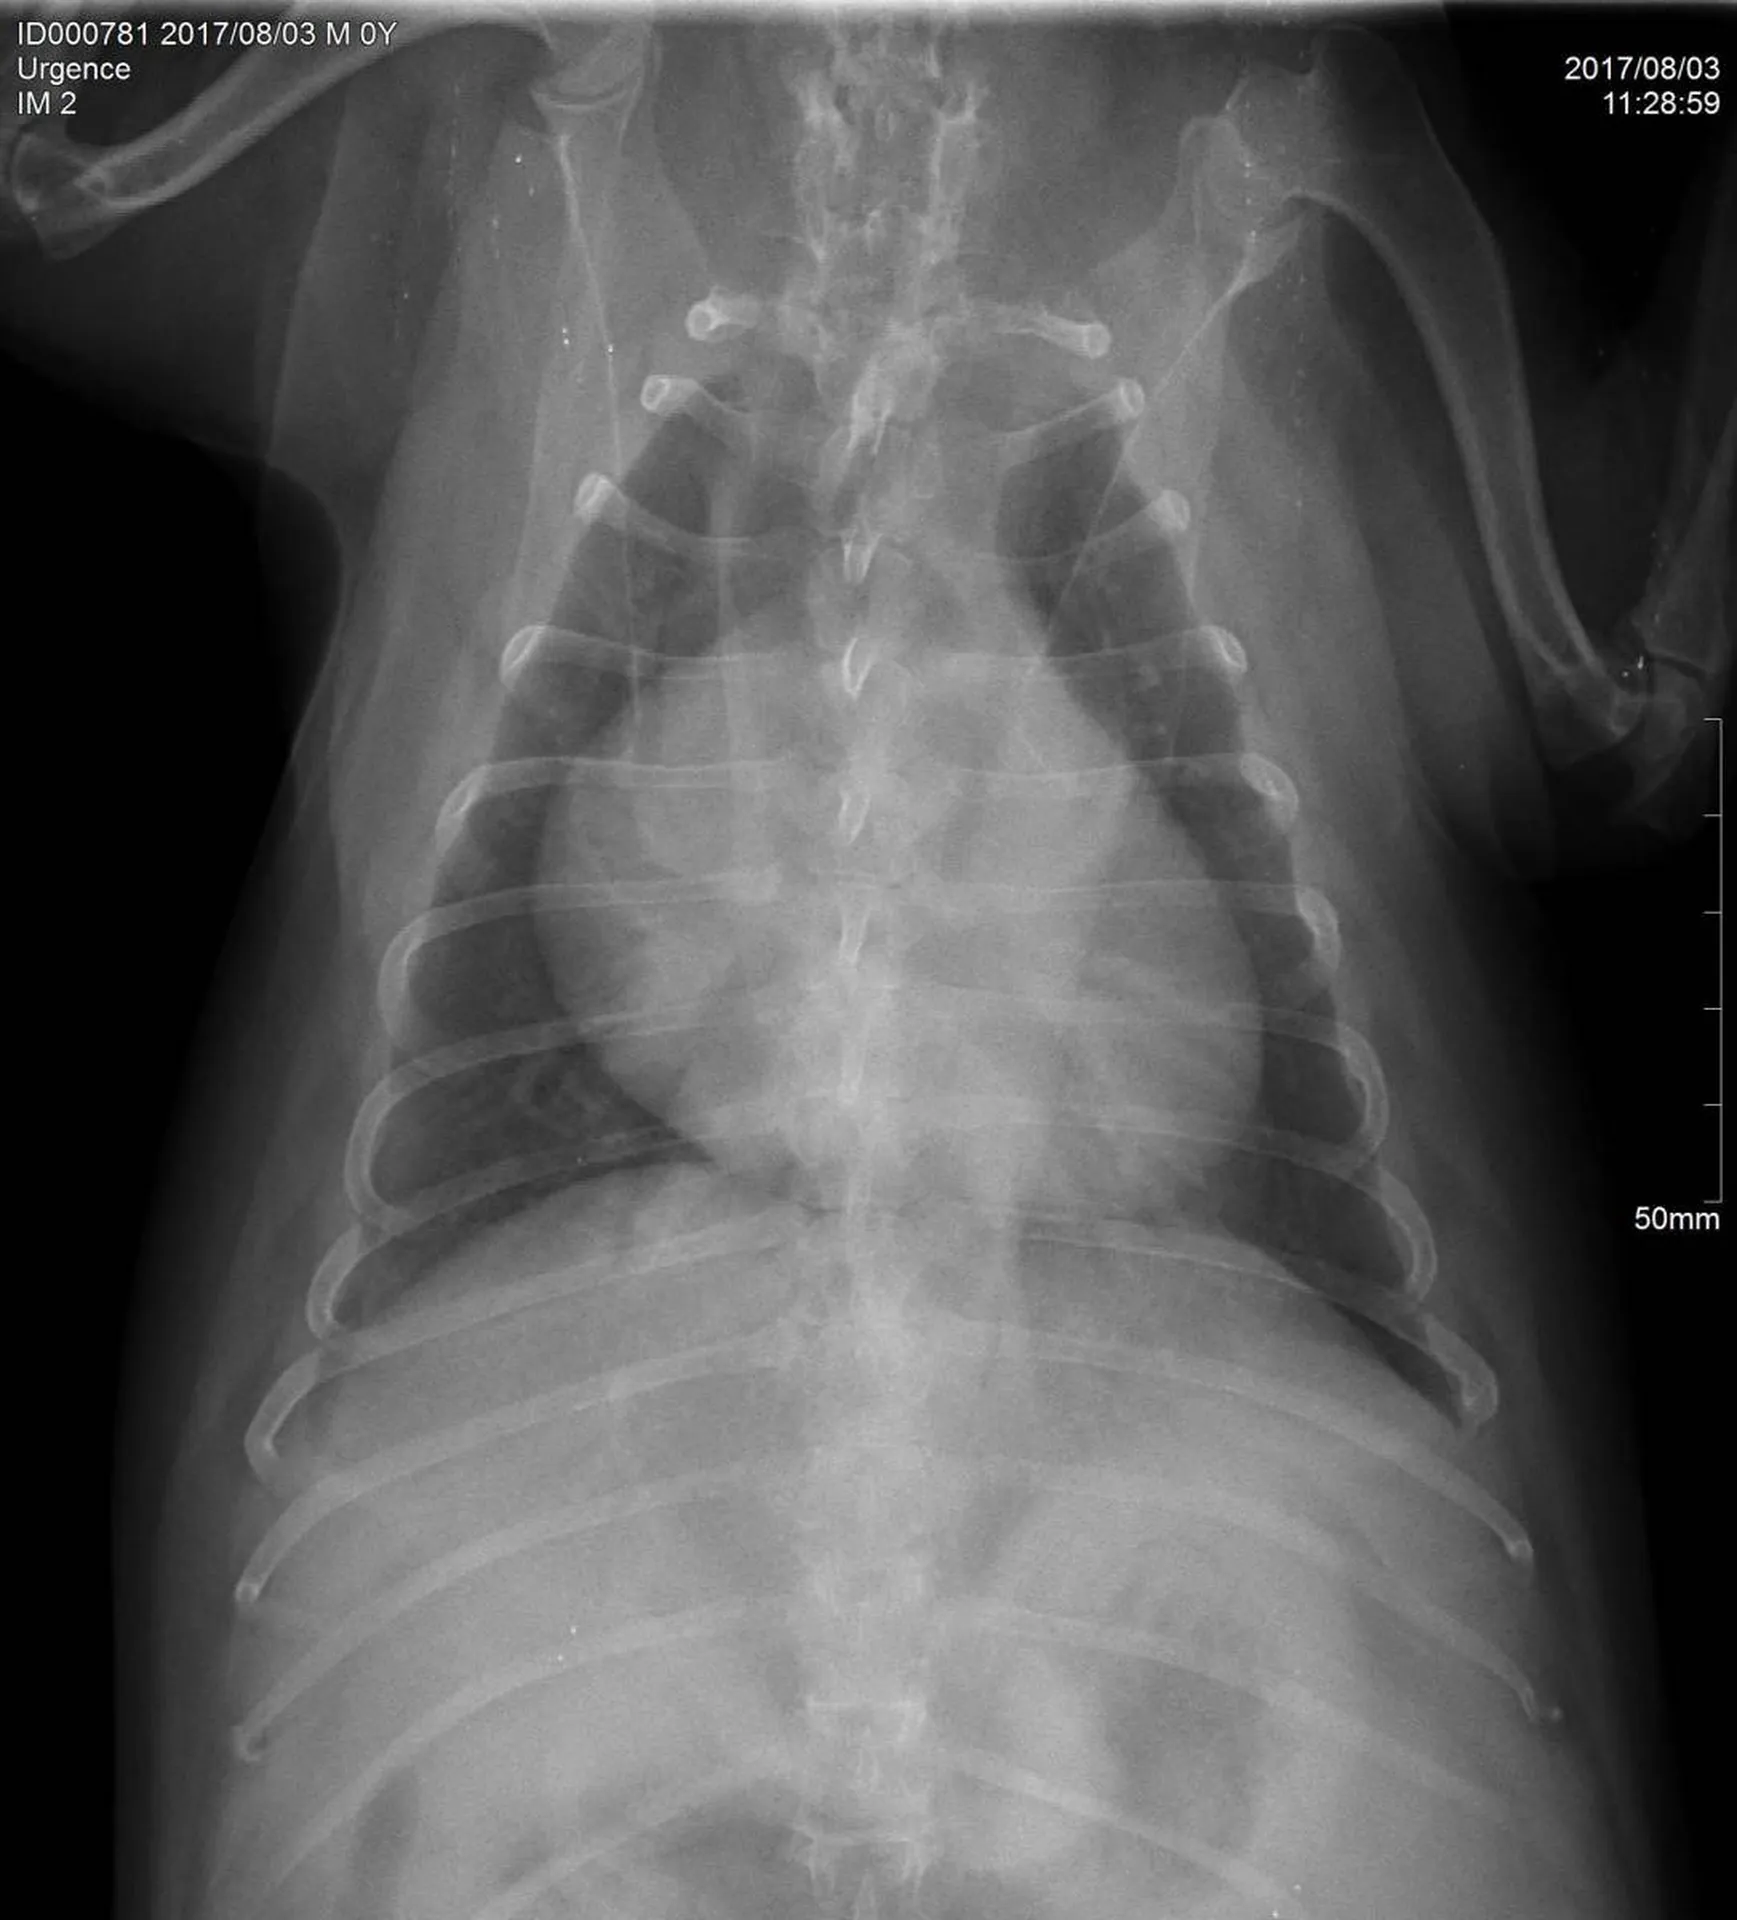

Une radiographie est un examen d’imagerie consistant à la prise de cliché au moyen d’un appareil à rayon X ceci afin de visualiser les différentes structures internes.

La radiographie reste indiquée dans de nombreuses affections, quelles soient respiratoires (radiographie cervicale ou thoracique), digestives (radiographie thoracique ou abdominale), locomotrices (membres, colonne), dentaires.

Votre chien, chat Nac est déposé sur la table de radiologie et différents clichés sont effectués dans différentes positions suivant la pathologie présentée.

Comme tout examen, il présente ses limites. Le principe de la radiographie étant l’utilisation du contraste (visualisation d’un tissu par rapport au tissu environnant et par rapport à sa radiodensité), certaines pathologies ne peuvent être que suspectées par radiographie mais nécessite d’autres examens (échographie, endoscopie, scanner, IRM).